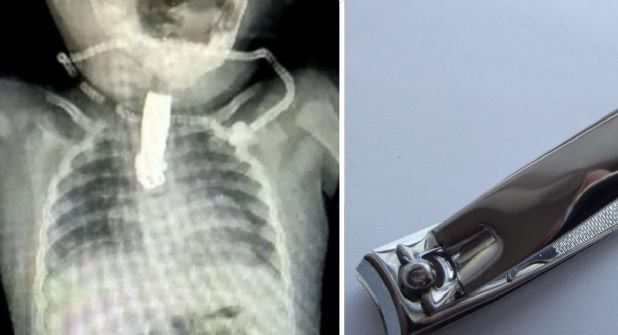

Su padres, al ver que la bebé tenía problemas al respirar, la llevaron de inmediato al hospital para su atención. Ya en el lugar se le realizó una radiografía, donde se reveló la existencia del objeto de cinco centímetros. Ante esto, los médicos dispusieron de una cirugía menor para extraerlo.

El impresionante accidente ocurrió en la India donde la bebé, de tan solo ocho meses, consumió un cortauñas de metal, el cual impidió su libre respiración. La familia de la menor, quienes viven en el distrito conocido como Nashik, dejaron un momento sin supervisión a la pequeña, traduciéndose en este terrible accidente.